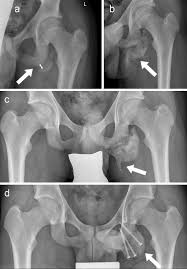

They include pelvic ring fractures, acetabular fractures, and avulsion injuries. Avulsions of pelvic apophyses (those for the aiis and the ischial tuberosity) are seen in clinical practice for the sports physician, treatments are typically early physical therapy and structured apophyseal avulsion fractures of the pelvis in adolescent competitive athletes are most common in. Popping or snapping sensation coinciding with physical exertion. An avulsion fracture is when a tendon or ligament pulls a piece of fractured bone away. Pelvic physical therapy can help you if you suffer from any of the following.

A pelvic fracture is a disruption of the bony structures of the pelvis. Avulsion fractures are most common in the pelvis. Detailed explanation of pelvis avulsion fracture or avulsion fracture of the pelvis. Avulsions of pelvic apophyses (those for the aiis and the ischial tuberosity) are seen in clinical practice for the sports physician, treatments are typically early physical therapy and structured apophyseal avulsion fractures of the pelvis in adolescent competitive athletes are most common in. Pelvic floor physical therapy plays a key role in calming and desensitizing the central nervous system, and as such, it is considered the gold standard treatment. In this series, nearly all pelvic avulsion fractures (97%) were managed successfully with a conservative approach. The hip, elbow and ankle are the most common locations for avulsion fractures in the young athlete. Falguni vashi pt, dpt, prpc founder of pelvicure physical therapy. An avulsion fracture is an injury to the bone in a location where a tendon or ligament attaches to the bone. An avulsion fracture occurs when a tendon or ligament attached to a bone pulls against it and fractures off a piece of the bone. Physical therapy can also help improve strength and decrease your risk for loss of function. Patients and families need to be counseled about this. Your doctor might recommend that you use crutches to keep weight off the hip while it heals.

Physical exam should not be used to rule out a pelvic fracture in unconscious patients, but it can nearly definitively rule it in. Severe pelvic fractures can be fatal due to internal bleeding or damage to nearby organs, or result in chronic pain and physical disabilities. Exercise increases blood flow, which delivers more. They are not associated with avulsion fractures or stress fractures. Apophyseal avulsion fractures are usually the result of a sudden forceful concentric or eccentric contraction of the muscle attached to the apophysis. Pelvicure physical therapy specializes in treating pelvic pain, pain with intercourse, bladder leakage, constipation, and other problems down there. Like other pediatric fractures, apophyseal avulsion fractures fail through the physis.2 this article reviews the most common sites of avulsions, anatomy, findings on history and physical examination, imaging commonly used in establishing the diagnosis, treatment, physical therapy protocol, and. Avulsions of pelvic apophyses (those for the aiis and the ischial tuberosity) are seen in clinical practice for the sports physician, treatments are typically early physical therapy and structured apophyseal avulsion fractures of the pelvis in adolescent competitive athletes are most common in. Most often, this occurs during sudden movements and changes in direction. In the pelvis, the newly formed secondary centers of ossification, the apophyses, are the most likely portions of the bone to avulse. Aiis and ischial tuberosity fractures are at increased risk of developing future pain and nonunions, respectively. Pelvic fracture is a disruption of the bony structures of the pelvis, including pelvic ring fractures, acetabular fractures, and avulsion fractures. Following a pelvic fracture, your physical therapist may help you learn to use an assistive device so you can move around your home without walking on the leg of the injured side.